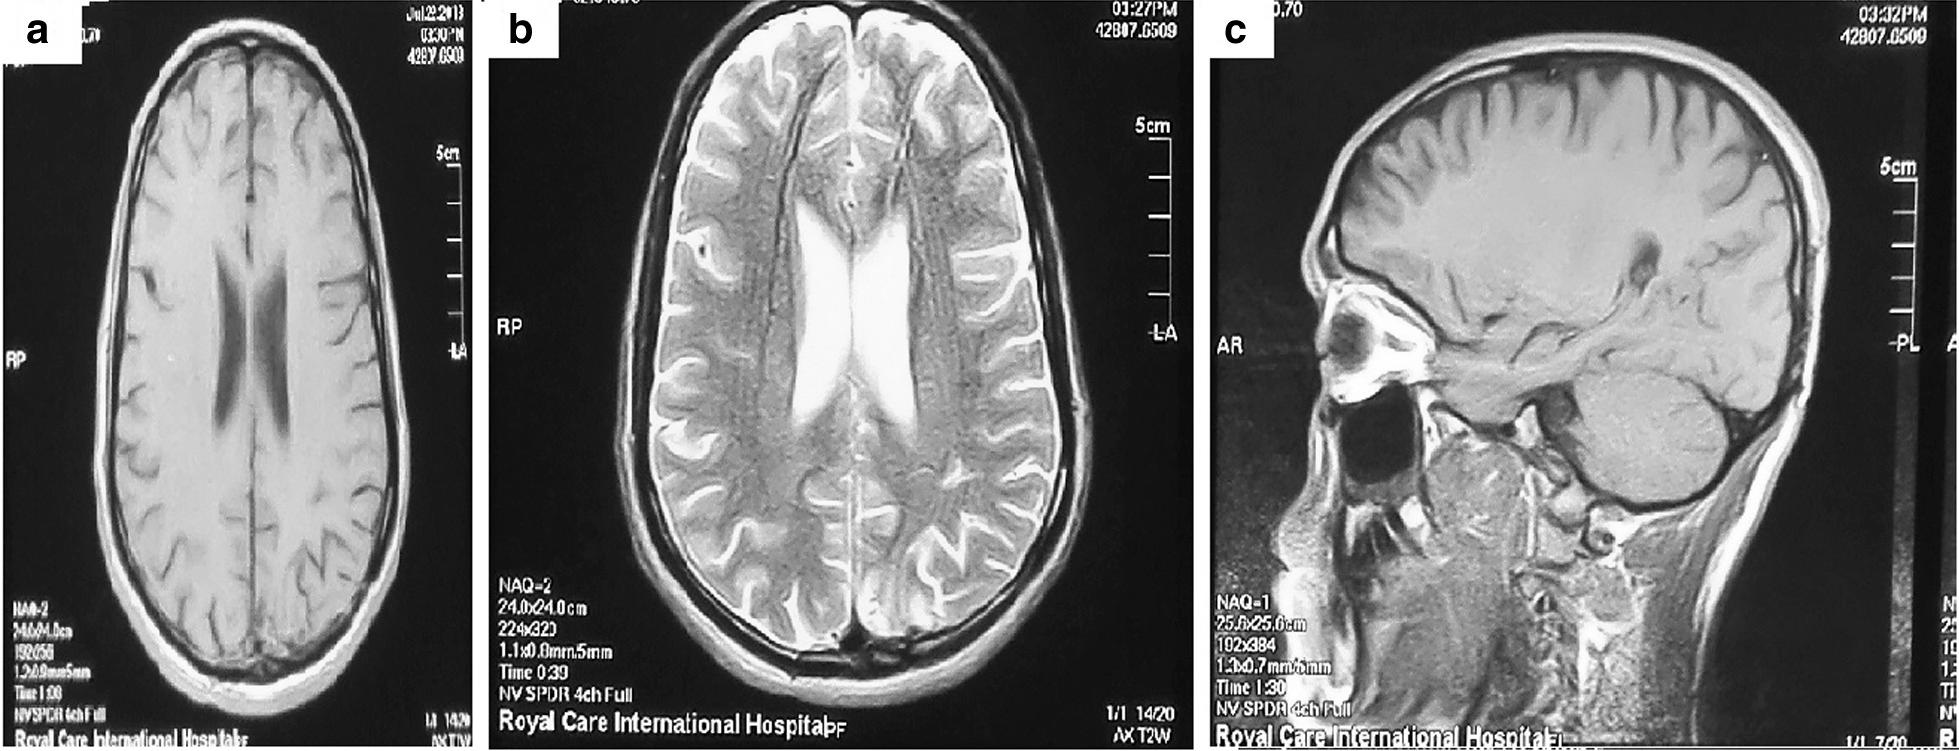

A 24-year-old, previously healthy Afro-asiatic man presented to our neurosurgical outpatient clinic complaining of headache and an attack of convulsions. On examination, he had bilateral lower limb weakness more on the right side. Laboratory investigations including stool and urine general test results were unremarkable. Magnetic resonance imaging of the brain was performed and showed an intra-axial left parietal mass; a granulomatous lesion was suggested in the differential diagnoses. The patient underwent craniotomy and total resection of the lesion. Histopathology confirmed the presence of active cerebral Schistosoma mansoni infection. Orally administered praziquantel was initiated at a dose of 20 mg/kg twice a day for a total of 3 days along with oral administration of corticosteroids for 2 weeks. The patient improved postoperatively without residual weakness and with no further convulsions.

一名 24 岁、既往健康的非裔亚洲男性因头痛和癫痫发作到我们的神经外科门诊就诊。体格检查发现他的双侧下肢无力,右侧更为明显。包括粪便和尿液常规检查在内的实验室检查结果无明显异常。对大脑进行磁共振成像检查,显示左顶叶脑内轴内肿块;鉴别诊断中提示为肉芽肿性病变。患者接受了开颅手术和病变的完全切除。组织病理学证实存在活动性脑曼氏血吸虫感染。给予患者口服吡喹酮,剂量为 20mg/kg,每日 2 次,共 3 天,并同时口服皮质类固醇 2 周。患者术后恢复良好,无残留无力和进一步的癫痫发作。